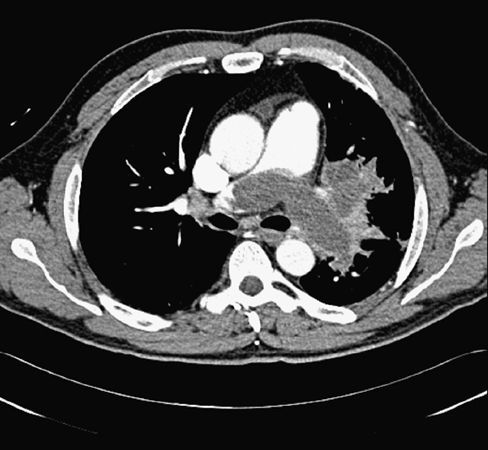

Radiología Caso 25

Caso 25